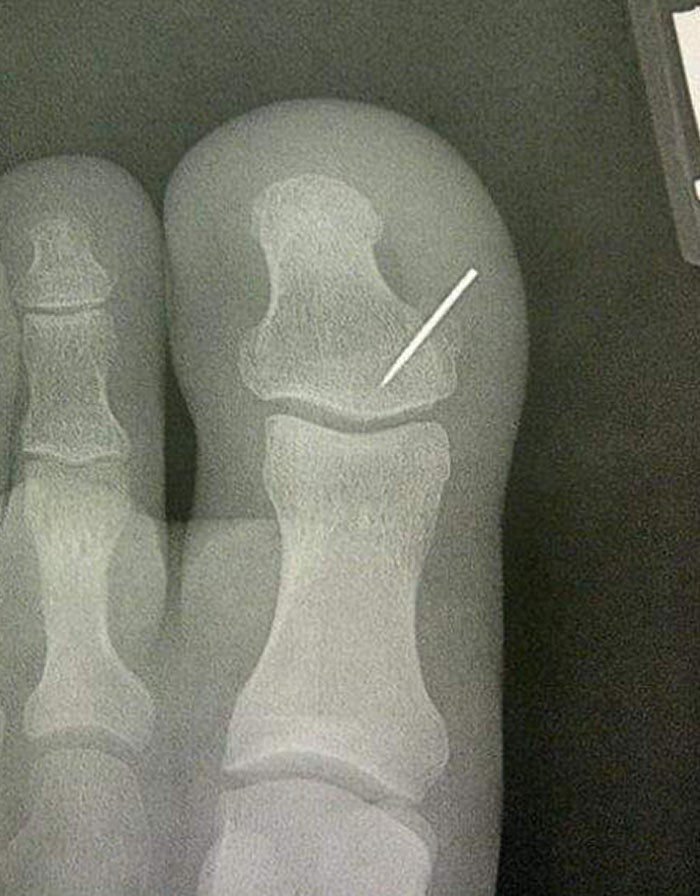

4 – Uma mulher perdeu sua agulha de costura no tapete e seu esposo a encontrou alguns dias depois… da pior forma